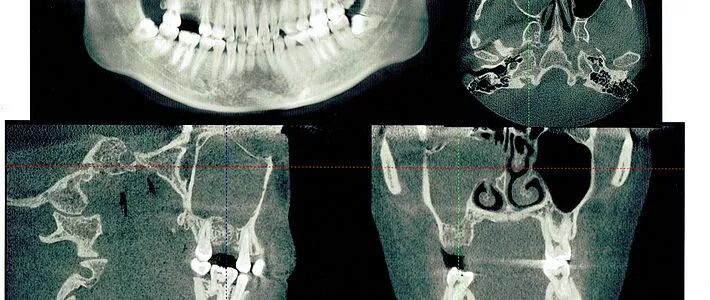

我是过敏性鼻炎患者,由于拍摄牙齿3维X光,发现上额窦出现堵塞,赶紧去综合性医院进行鼻子检查,我一直早上起来的第一件事就是打喷嚏 ,终于找到原因了。2013年被诊断为慢性化脓性鼻窦炎、鼻中隔偏曲、过敏性鼻炎,进行了全麻鼻中隔矫正术,鼻窦开放术,双侧下鼻甲等离子消融术,

右侧上额窦出现囊肿,正常情况下应该是透明,由于直接连着我需要做种植牙的位置,所以需要首先做鼻窦手术,然后才能做牙齿手术,我的人生还是一波又一波 。

二期手术前,医生还是需要拍X光了解种植体情况。真是不知道拍了多少X光。。。